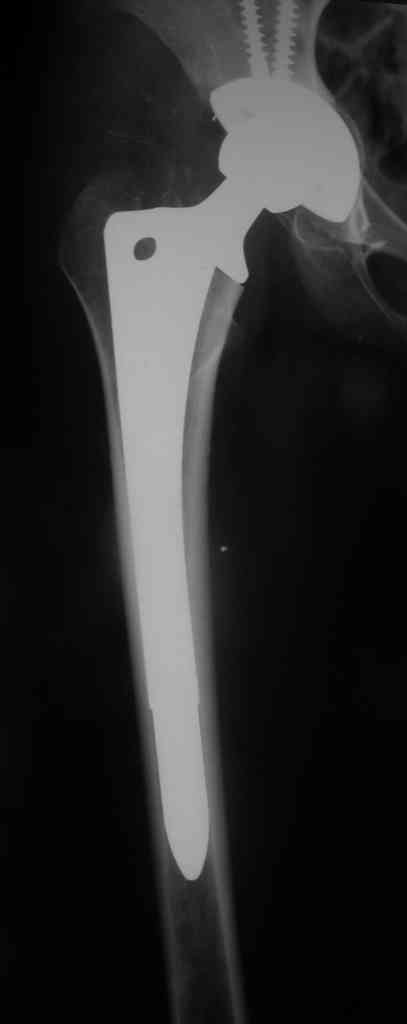

The bridging plate is a weak constuct for angular stresses and hence the deformity. The best option would be a revision THR with an open mind. After exposure one should see the integrity of the cup which is not clearly visible here. The stem is in Valgus and hence the fracture. IT needs to be revised to a long stem like the Wagner system with its 8 fins or a Proximal fit modular stem from J& J. ( both uncemented) Once again plating is not a good option against bending stresses in the femur.

Stems you show are fine but removing a well fixed AML stem means an extended trochanteric osteotomy, cutting the stem below its metaphyseal flair, then over reaming the distal piece of prosthesis. Can be done but is difficult, requires specialized equipment, and will create a lot of proximal bone loss and proximal femoral instability. Also, with the fracture, exposure of the hip joint is difficult because you can't rotate the hip by moving the lower leg. This means clamps on the proximal fragment further devascularizing the bone. You will be left with a bag of bone proximally using less than ideal distal fixation to encourage bone ingrowth to your revision prosthesis. Now you need ingrowth AND union.

This depends on the stem fixation. If the stem is fixed then it's a Vancouver type B1 fracture and should be fixed with a plate well past the Fx and at least 2-3 shaft diameters above the Fx site proximally (fixed with cerclage wires proximally).

If the stem is loose (Vancouver B2), then it needs to be revised to a longer prosthesis.

это не так. Сравниться по биомеханике может только и\м стержень, но

не пластина - данной постановке.